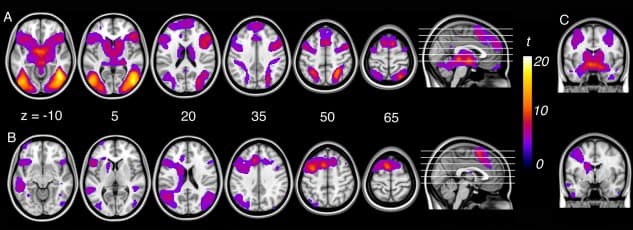

For the “look‐negative > look‐neutral” contrast, significant activation was observed bilaterally across a large expanse of visual association cortex, including the fusiform gyrus and lateral occipital cortex, extended hippocampus‐amygdala complex, dorsal midbrain (∼periaqueductal gray), hypothalamus, medial thalamus, caudate head, ventral anterior insular cortex, pre‐supplementary and lateral premotor cortices, dorsomedial and dorsolateral prefrontal cortex, and the intraparietal sulcus extending to primary somatosensory cortex (Fig. (Fig.1A,1A, Supporting Information Table 3).

Figure 1

A: Activation corresponding to emotional reactivity (“look‐negative > look‐neutral”) and (B) reappraisal (“reappraise > look‐negative”) within subjects. C: Amygdala activation for emotional reactivity (top‐right) and reappraisal (bottom‐right).

For the “reappraise > look‐negative” contrast, significant activation was observed in predominantly left‐lateralized regions including the left pre‐supplementary area extending to the cingulofrontal cortex (at the junction of dorsal anterior cingulate cortex and dorsomedial frontal cortex), dorsal premotor cortex extending to dorsolateral prefrontal cortex, frontal operculum and ventral anterior insular cortex, left caudate body, bilateral angular gyrus, posterior‐superior temporal gyrus, and fusiform gyrus (Fig. (Fig.1B,1B, Supporting Information Table 3).

Examination of the “look‐negative > reappraise” contrast revealed that reappraisal led to significant reductions in activation (i.e., down‐regulation) of brain regions previously identified as responsive to the aversive social‐affective imagery. This included the left and right primary somatosensory cortex (area 2 and 3b); right dorsal amygdala extending to ventral pallidum and putamen; and secondary visual cortex (Fig. (Fig.2,2, Supporting Information Table 3). Examination of brain–behavioral associations within subjects revealed no significant relationship between down‐regulation of the amygdala during reappraisal and behavioral indices of reappraisal success.

Figure 2

Regions down‐regulated during reappraisal (i.e., look‐negative > reappraise) within subjects.